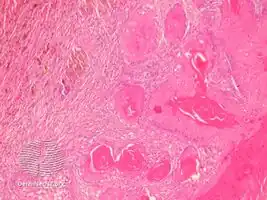

Proliferating trichilemmal cysts (also known as a "Pilar tumor", "Proliferating follicular cystic neoplasm", "Proliferating pilar tumor", and "Proliferating trichilemmal tumor"[2]) are a cutaneous condition characterized by proliferations of squamous cells forming scroll-like structures.[2][3]: 678